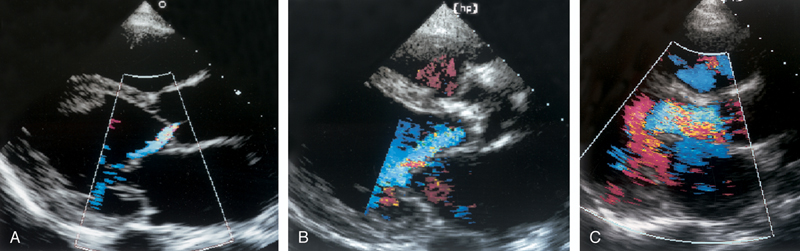

فحوصات تشخيصية لبعض امراض القلب والشرايين التاجية